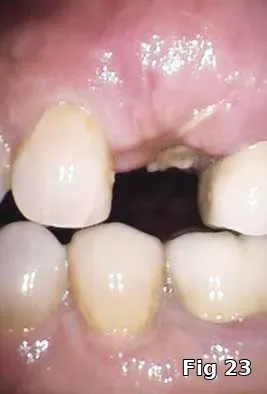

Here PRGF graft was helpful in securing the buccal fenestration defect at the apex prior to bone grafting (Fig. 18) allowing for secure placement and containment of the bone graft (Fig. 19) and PRGF membrane (Fig. 20) for ridge preservation. Flaps were readapted and closed over the PRGF membrane (Fig. 21) and one-week postoperative shows complete closure of the soft tissue over the extraction socket (Fig. 22) and complete resolution of the sinus tract and swelling in the buccal gingival (Fig. 23).

Regeneration of dehiscence: Long-term successful maintenance of soft tissue around implants can be challenging. In this case of dehiscence of the soft tissue and chronic inflammation around a subperiosteal implant (Fig. 24), the exposed implant strut was sectioned (Fig. 25) and removed, and PRGF grafts were used to fill in the defect left behind (Fig. 26) and accelerate healing and granulation of the soft tissues (Fig. 27).